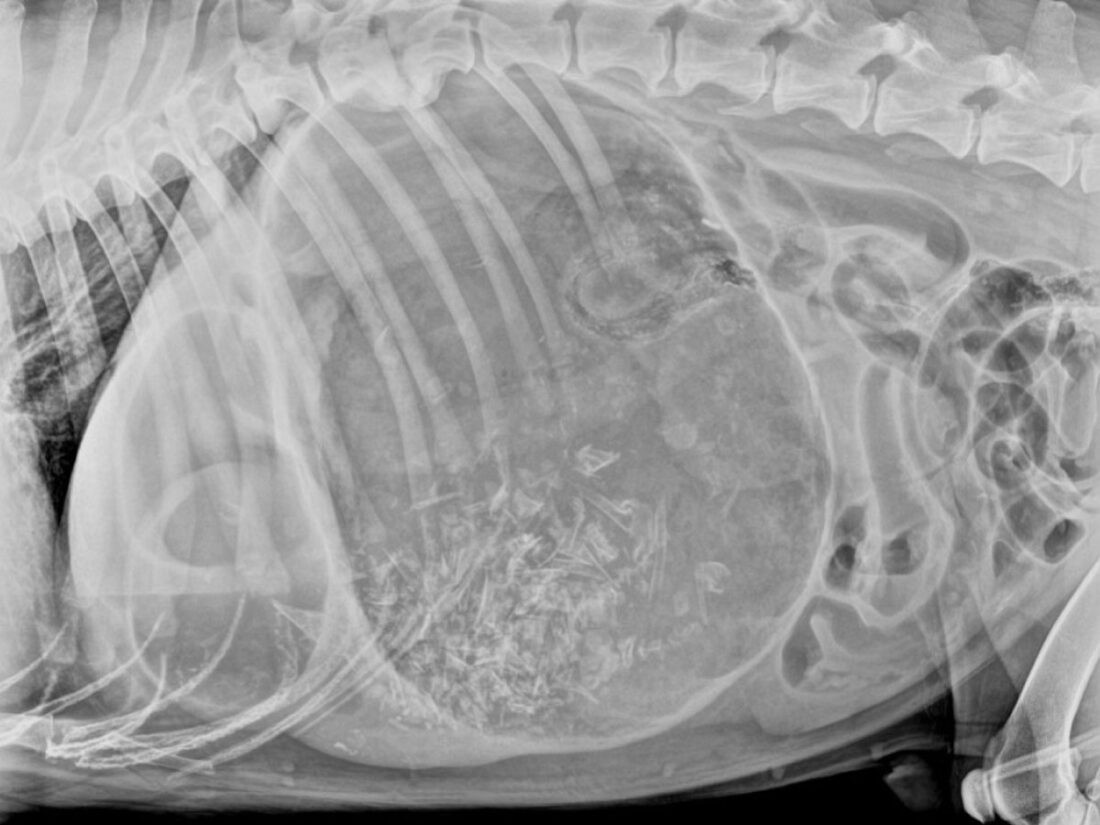

Volvamos al caso, un perro grande de 55 kilos entró en la clínica. Llevaba un rato intentando vomitar, sin éxito.

Su tiempo de rellenado capilar era de más de 2 segundos, con un color pálido en las mucosas. Para su tamaño, su frecuencia cardíaca era elevada.

Además, estaba jadeando. Al tocar el abdomen, se notaba hinchado.

Era bastante claro que estaba sufriendo un posible shock hipovolémico. Para confirmarlo, tomamos una muestra de sangre y comprobamos que sufría hemoconcentración (comenzamos a darle fluidos en bolo a una dosis de 20 mililitros por kilo), así como una hiperlactemia moderada (Evaluación del plasma lactato como pronosticador de supervivencia en perros con shock) .

Por fin llegaban buenas noticias, tras conectarlo al multiparamétrico, su presión sanguínea era relativamente normal y no se veían muchas taquiarritmias supraventriculares, a pesar de ello se le administró una dosis de lidocaína a 2 mg por kilo por su efecto en la cascada inflamatoria (Gestión posoperatoria del DVG).

Según los estudios, el pronóstico de una torsión de estómago empeora en función de la presión sanguínea y el lactato.

Un lactato alto con una presión sanguínea baja es un indicador muy malo para el éxito de la cirugía (Análisis de supervivencia de perros críticamente enfermos con hipotensión con o sin hiperlactemia).

Para los que queráis saber el final de la historia, la dilatación se confirmó por radiografía, el paciente fue a quirófano, la torsión fue resuelta y se llevó a cabo una gastropexia. El paciente se recuperó y comenzó a comer a la mañana siguiente.